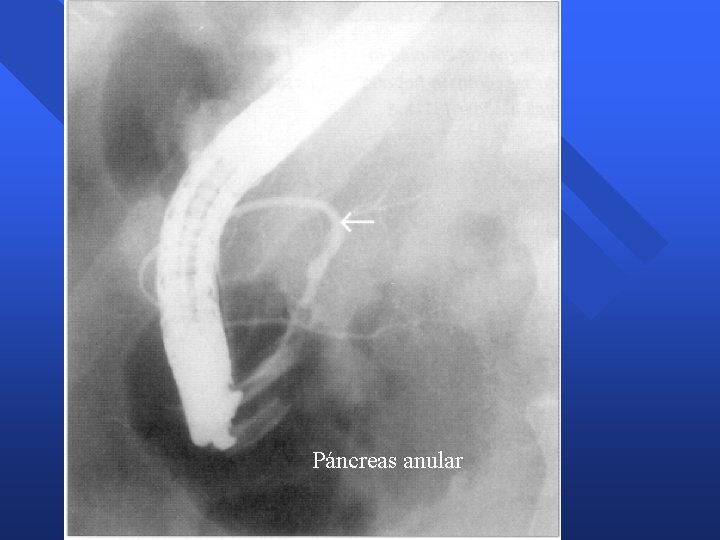

Alteraciones Congénitas del Páncreas n Páncreas anular – 1/10. 000 nacidos. 50% otras malformaciones – Causa más frecuente obstrucción duodenal n Páncreas divisum – Malformación más frecuente. 5 -10% población – No fusión conductos dorsal y ventral 8º semana » Dorsal drena por papila Minor » Ventral drena por papila Mayor – Clínica –Tratamiento » Pancreatitis agudas recurrentes » Esfinterotomía p. Menor » Endoprótesis » Pancreatitis crónica » Dolor crónico abdominal

Páncreas anular